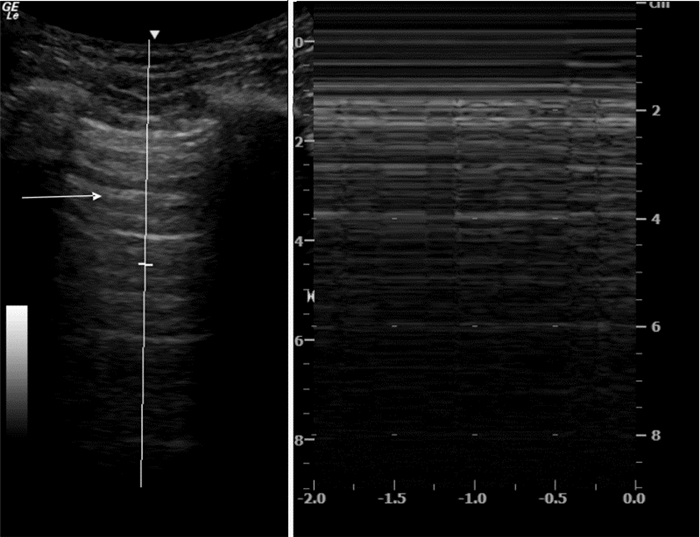

超声检查IVC内径及其随呼吸的变异率不但能提供患者容量状态的信息,有时还能评估液体反应性(图 19、20)。ASE(美国心超协会)指南的建议:用力吸气时,IVC直径≤2.1 cm伴随呼吸变异率>50%,对应于中心静脉压(CVP)值3 mmHg(0~5 mmHg,1 mmHg=0.133 kPa),IVC直径>2.1 cm伴随呼吸变异率<50%,对应的CVP值为15 mmHg(10~20 mmHg);如IVC直径≤2.1 cm伴随呼吸变异率<50%或IVC直径>2.1 cm伴随呼吸变异率>50%,提示对应的CVP值可能为8 mmHg(5~10 mmHg),此时应考虑采用其他指标来估测CVP[1]。其他文献报道数值略有不同,平静呼吸时,IVC直径≤2 cm伴随呼吸变异率>50%,对应于CVP值≤10 mmHg,可见于低血容量和分布性休克患者;IVC直径>2 cm伴随呼吸变异率<50%,对应的CVP值大于10 mmHg,可见于心源性和梗阻性休克患者[2]。

| 图 20 M超显示IVC随呼吸直径发生变化 |

但IVC的超声成像有时比较困难,特别是肥胖、腹胀和肠胀气明显的患者;而且IVC大小还受机械通气患者呼气末正压(PEEP)的影响,用来估计CVP有一定的缺陷[3]。在完全控制通气模式下(无自主呼吸触发)时,吸气相IVC扩张超过12%~18%,可较好的预测容量反应性。IVC管径随着PEEP水平的增加而升高,呼吸变异率随PEEP的增加而变小,但目前PEEP对IVC容量评估的影响尚无定论,有待进一步临床研究。